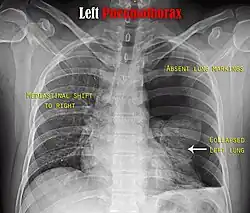

Chest X-ray

A plain chest radiograph, ideally with the X-ray beams being projected from the back (posteroanterior, or "PA"), and during maximal inspiration (holding one's breath), is the most appropriate first investigation.[35] It is not believed that routinely taking images during expiration would confer any benefit.[36] Still, they may be useful in the detection of a pneumothorax when clinical suspicion is high but yet an inspiratory radiograph appears normal.[37] Also, if the PA X-ray does not show a pneumothorax but there is a strong suspicion of one, lateral X-rays (with beams projecting from the side) may be performed, but this is not routine practice.[18][22]

Chest X-ray showing a pneumothorax on the right (left in the image), where the absence of lung markings indicates that there is free air inside the chest -

Chest X-ray showing the features of pneumothorax on the left side of the person (right in image)

It is not unusual for the mediastinum (the structure between the lungs that contains the heart, great blood vessels, and large airways) to be shifted away from the affected lung due to the pressure differences. This is not equivalent to a tension pneumothorax, which is determined mainly by the constellation of symptoms, hypoxia, and shock.[16]

The size of the pneumothorax (i.e. the volume of air in the pleural space) can be determined with a reasonable degree of accuracy by measuring the distance between the chest wall and the lung. This is relevant to treatment, as smaller pneumothoraces may be managed differently. An air rim of 2 cm means that the pneumothorax occupies about 50% of the hemithorax.[18] British professional guidelines have traditionally stated that the measurement should be performed at the level of the hilum (where blood vessels and airways enter the lung) with 2 cm as the cutoff,[18] while American guidelines state that the measurement should be done at the apex (top) of the lung with 3 cm differentiating between a "small" and a "large" pneumothorax.[38] The latter method may overestimate the size of a pneumothorax if it is located mainly at the apex, which is a common occurrence.[18] The various methods correlate poorly but are the best easily available ways of estimating pneumothorax size.[18][22] CT scanning (see below) can provide a more accurate determination of the size of the pneumothorax, but its routine use in this setting is not recommended.[38]

Not all pneumothoraces are uniform; some only form a pocket of air in a particular place in the chest.[18] Small amounts of fluid may be noted on the chest X-ray (hydropneumothorax); this may be blood (hemopneumothorax).[16] In some cases, the only significant abnormality may be the "deep sulcus sign", in which the normally small space between the chest wall and the diaphragm appears enlarged due to the abnormal presence of fluid.[19]